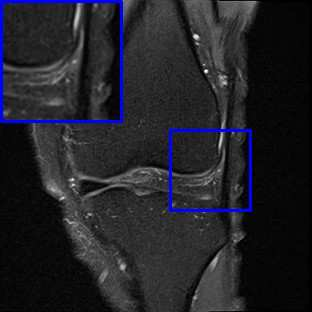

Limited by imaging systems, the reconstruction of Magnetic Resonance Imaging (MRI) images from partial measurement is essential to medical imaging research. Benefiting from the diverse and complementary information of multi-contrast MR images in different imaging modalities, multi-contrast Super-Resolution (SR) reconstruction is promising to yield SR images with higher quality. In the medical scenario, to fully visualize the lesion, radiologists are accustomed to zooming the MR images at arbitrary scales rather than using a fixed scale, as used by most MRI SR methods. In addition, existing multi-contrast MRI SR methods often require a fixed resolution for the reference image, which makes acquiring reference images difficult and imposes limitations on arbitrary scale SR tasks. To address these issues, we proposed an implicit neural representations based dual-arbitrary multi-contrast MRI super-resolution method, called Dual-ArbNet. First, we decouple the resolution of the target and reference images by a feature encoder, enabling the network to input target and reference images at arbitrary scales. Then, an implicit fusion decoder fuses the multi-contrast features and uses an Implicit Decoding Function~(IDF) to obtain the final MRI SR results. Furthermore, we introduce a curriculum learning strategy to train our network, which improves the generalization and performance of our Dual-ArbNet. Extensive experiments in two public MRI datasets demonstrate that our method outperforms state-of-the-art approaches under different scale factors and has great potential in clinical practice.